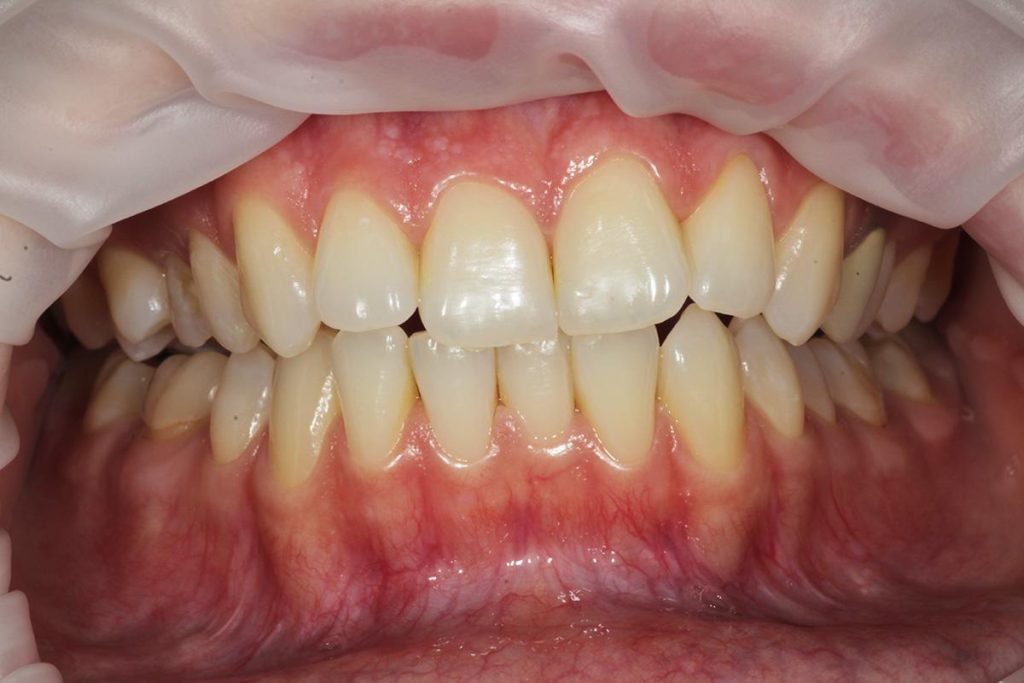

Dzięki precyzyjnej diagnostyce, doktor Magdalena Zawirska opracowała kompleksowy plan leczenia, który obejmował: stomatologię zachowawczą, periodontologię i protetykę stomatologiczną. Zastosowano licówki i korony pełnoceramiczne, przeprowadzając kompleksową rekonstrukcję zwarcia.

Pacjentka może się teraz cieszyć się pięknym i zdrowym uśmiechem